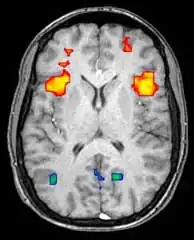

Функциональная магнитно-резонансная томография

Функциональная магнитно-резонансная томография (фМРТ) основана на парамагнитных свойствах оксигенированого и дезоксигенированого гемоглобина и дает возможность увидеть изменения кровообращения головного мозга в зависимости от его активности. Такие изображения показывают, какие участки мозга активированы (и каким образом) при исполнении определённых заданий.

Большинство фМРТ-томографов дают возможность представлять исследуемому разные визуальные изображения, звуковые и тактильные стимулы и производить действия типа нажатия кнопки или движения джойстиком. Следовательно, фМРТ можно использовать, чтобы показывать структуры мозга и процессы, связанные с восприятием, мышлением и движениями. Разрешение фМРТ на данный момент 2—3 мм, ограниченное кровоснабжением, влияющим на нейрональную активность. Она существенно заменяет ПЭТ при исследовании типов активации головного мозга. ПЭТ, однако, одерживает значительное преимущество, будучи в состоянии идентифицировать специфические клеточные рецепторы или (моноаминовые трансмиттеры) связанные с нейромедиаторами, благодаря визуализации меченных радиоактивно рецепторных «лигандов» (рецепторный лиганд — химическое вещество, связанное с рецептором).

фМРТ используют как для медицинских исследований, так и (всё шире) в диагностических целях. Так как фМРТ исключительно чувствительна к изменениям кровообращения, она очень хорошо диагностирует ишемию, как например при инсульте. Ранняя диагностика инсультов всё важнее в неврологии, так как медикаменты, растворяющие свернувшиеся сгустки крови, можно использовать в первые несколько часов и при определённом типе инсульта, в то время как они могут быть опасными при дальнейшем использовании. фМРТ в таких случаях дает возможность принять правильное решение.

фМРТ можно использовать также для распознавания мыслей. В эксперименте с точностью 72 %—90 %[5] фМРТ смогла установить, какой набор картинок смотрит испытуемый[6]. Скоро, по мнению авторов исследований, благодаря этой технологии можно будет установить, что именно видит перед собой испытуемый[6]. Эту технологию можно будет использовать для визуализации снов, раннего предупреждения болезней головного мозга, создания интерфейсов для парализованных людей для общения с окружающим миром, маркетинговые рекламные программы и борьба с терроризмом и преступностью[6].